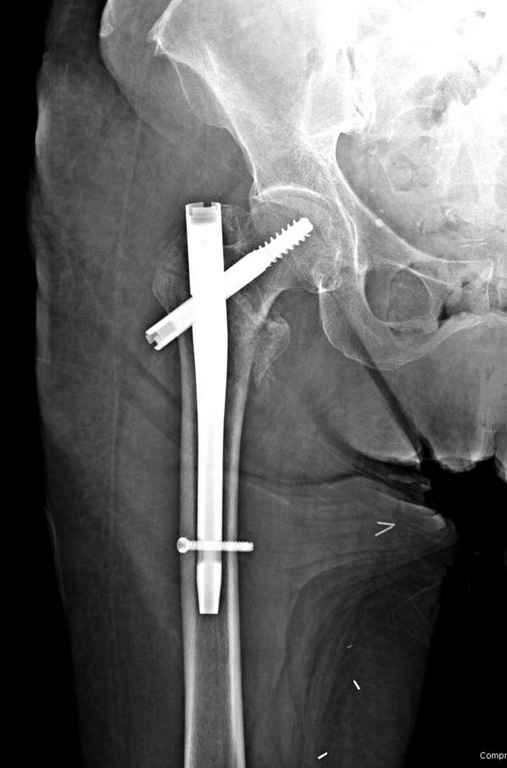

Перелом тут больше подвертельный. Нагрузка без торцевого упора на уровне перелома привела к телескопированию отломков на стержне. Ну и варус небольшой тоже свою лепту внес - если бы его не было, контактирующие латеральные стенки обоих отломков предотвратили бы укорочение, да и срослось бы за пару месяцев. А раз не срослось, упора отломков нет, более слабым местом оказались не нижние винты, а кость в головке и шейке. Так что надо было хотя бы удалить нижние винты до начала полной нагрузки.

Наверно, эндопротезирование. Есть более щадящий вариант - реостеосинтез (с устранением варуса и укорочения!), а после сращения и при наличии выраженного болевого синдрома - стандартное протезирование.

Фиксация * reversed obliquity* подвертельных переломов - дело непростое.

На мой взгляд, причиной телескопирования явилось несоответствие диаметра гамма нэйл с диаметром канала подвертельного отдела бедра: обратите внимание на величину протрузии шеечного винта и величину медиализации дистального фрагмента - они одинаковы, смещение или телескопирование фрагментов происходило до того момента, пока гамма нэйл не упёрся в медиальный кортекс и образовалось пространство между латеральным

кортексом и латеральной поверхностью гвоздя.